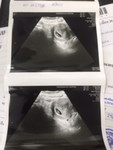

ท้อง29+5W ลื่นล้มก้นกระแทกค่ะ

ล้มวันอาทิตย์(วันนี้) โทรหา รพ.คลินิกฝากครรภ์ปิด ไม่มีหมอเฉพาะทาง จนท.โอเปอเรเตอร์รับสายบอกให้ไปห้องฉุกเฉินได้ คำถามคือ น้องยังดิ้น เลือดไม่ออกไม่ปวดท้อง เหมือนจะยังไม่มีอาการผิดปกติใดๆ เราควรไปห้องฉุกเฉินเลยมั้ยคะ จนท.บอกแล้วแต่คนไข้ค่ะ #อุบัติเหตุลื่นล้ม